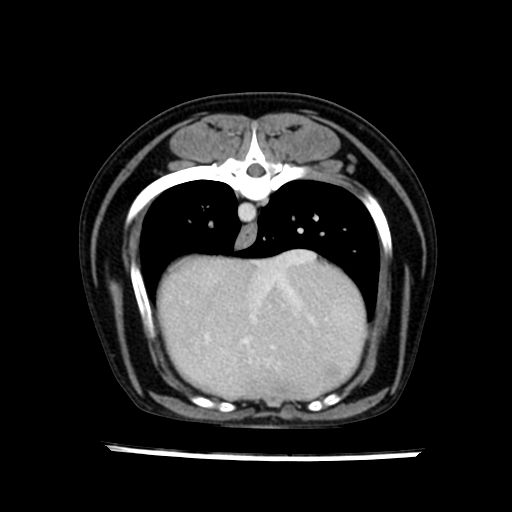

prescritto esame TAC

sequenza immagini limitata al fegato reni e surreni

le immagini ecografiche rispetto alla tac datano circa 7 mesi prima ,le surrenali sono normali nonostante il test acth sia risultato positivo .all’esame TAC dopo diversi mesi risultano aumentate armonicamente nel volume e si individua un forte sospetto di adenoma ipofisario .

sospetto adenoma ipofisario vs. meno probabilmente meningioma della base; intertiziopatia polmonare; lesione espansiva epatica, verosimilmente del lobo laterale sinistro, di sospetta natura neoplastica; lesioni spleniche di natura da definire; iperplasia/ipertrofia delle ghiandole surrenali, bilateralmente; vertebra di transizione del rachide toracico; tenosinovite cronica del muscolo bicipite brachiale di destra.